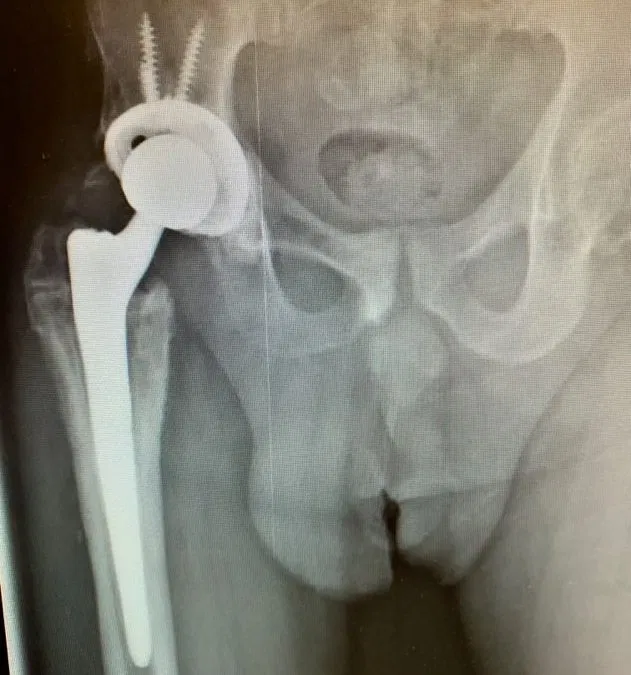

Case Study of Recurrent Total Hip Arthroplasty (THA) Dislocation

Case Study of Recurrent Total Hip Arthroplasty (THA) Dislocation Patient is a 55 year old male who came to us complaining of recurrent right hip prosthesis dislocation. Patient stated that this had been occurring since he had a right Total Hip Arthroplasty (THA) a few years ago done at an outside institution. Patient had come in...